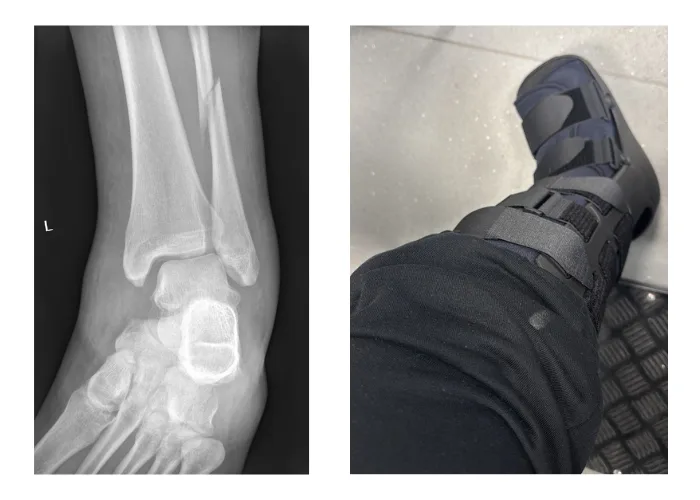

In early 2025, I broke my fibula while on a solo trip to Scotland. Two surgeries, six months of bed rest, being entirely dependent for the first time in my adult life, and then four more months of working on a foot that had developed strong opinions about every surface it touched.